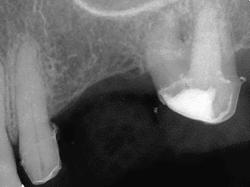

A 75-year-old female was referred for endodontic treatment associated with a cariously exposed posterior abutment tooth, #15 (Fig. 3). After taking a thorough medical history including blood pressure measurement, a clinical examination of the upper-left quadrant was performed. The need for endodontic treatment prior to the fabrication of a permanent fixed bridge was readily apparent.

Fig. 3: Pre-operative radiograph, tooth #15. Straight-line access